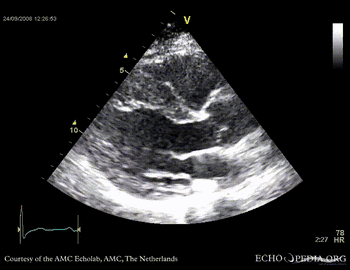

Four leaflet aortic valve

Case description: This patient had four aortic valve leaflets. Two aortic leaflets is a relatively common congenital anomaly. Four aortic valve leaflets is very rarely seen.

PSAX through aortic valve, clearly showing four valve leaflets PSAX through aortic valve, clearly showing four valve leaflets